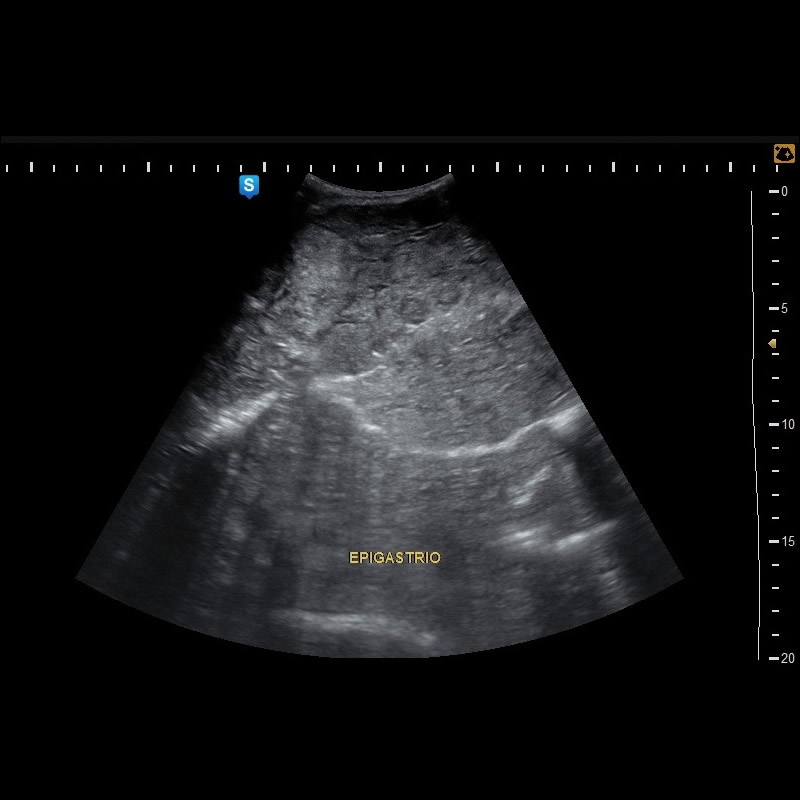

Distensión abdominal